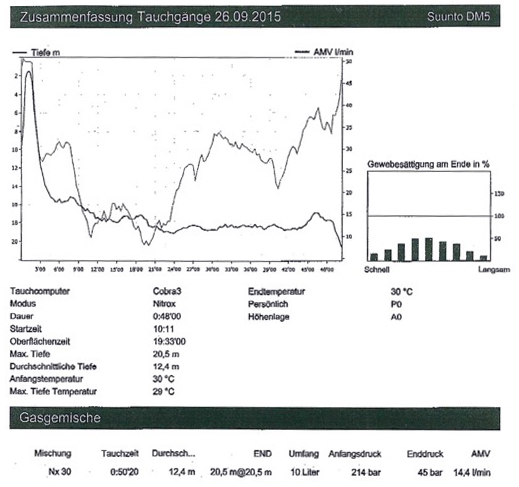

Matthias bleibt fast während des gesamten ca. 45-minütigen

Tauchganges auf 20 Meter und macht Fotos und Videos.

Auch während des gerade durchgeführten Tauchganges hielt

sich Matthias an alle Regeln für einen sicheren Tauchgang.

Zusätzlich hatte er heute sogar eine 30er Nitrox-Mischung

verwendet.